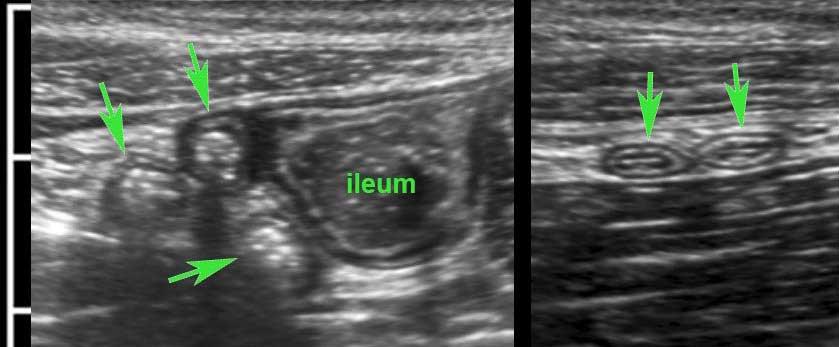

Hình ảnh siêu âm kinh điển của lồng ruột hồi-manh tràng ở hai trẻ khác nhau.

Trong cả hai trường hợp, đoạn hồi tràng bị lồng được định vị không đối xứng bên trong ống lồng ngoài, do mạc treo ruột tăng âm có chứa mỡ, bám vào hồi tràng và đi theo hồi tràng khi bị kéo vào trong.

Trong mạc treo, siêu âm cho thấy một hạch bạch huyết mạc treo (hbh) phóng đại ở cả hai.

Các hạch này phì đại như một phần của tình trạng tăng sản hạch bạch huyết toàn thân và khônghu trú trong lòng hồi tràng.

Do đó đây không phải là điểm dẫn đầu nguyên phát. Ở bệnh nhân bên phải, ruột thừa (mũi tên) cũng bị kéo vào trong.

Lưu ý cấu trúc đa lớp của thành bụng phía trước của phức hợp lồng ruột, đại diện cho ba lớp thành ruột bị gấp lại.